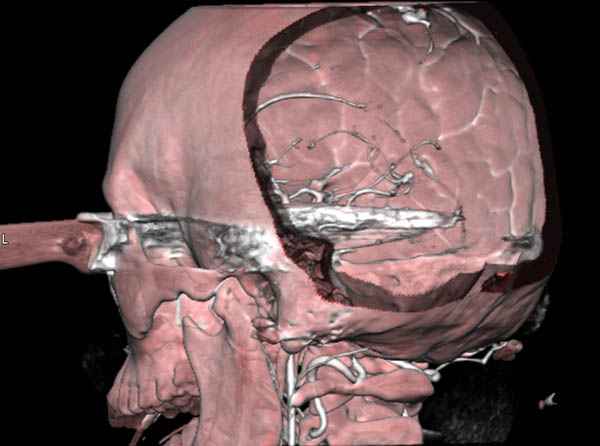

По протоколу сделаны все необходимые исследования: рентген, ангиограмма с 3Д реконструкцией, где обнаружили что все жизненно важные сосуды не задеты, даже некоторые "сидят" изгибаясь на ноже.

Одним махом нож удалить не удалось, пришлось раскачать и потом двумя руками удалили нож. Рана без кровотечения, обработана и зашита.